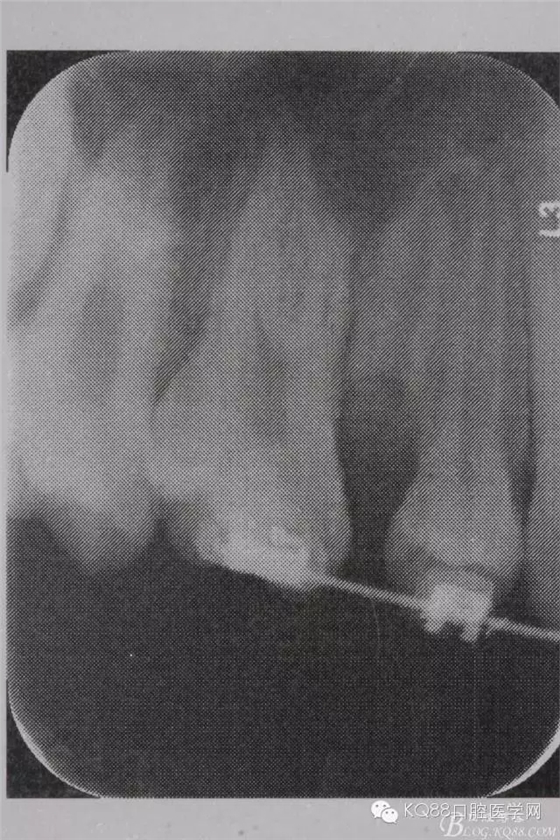

圖4. 加拍局部根尖片,15牙根顯露無(wú)疑,遂考慮拔除15,才能關(guān)閉16與14之間的間隙。